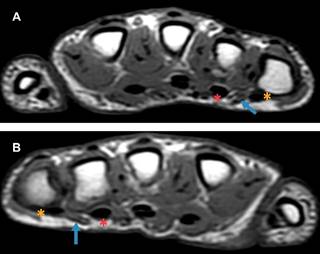

Masculino de 15 años de edad, que presenta deformidad del dedo meñique de ambas manos. No tiene antecedentes de traumatismos, patologías o síndromes congénitos. Nadie más en su familia presentaba dicha morfología en los dedos. En el estudio de resonancia magnética (RM) se observó deformidad del quinto dedo por hiperflexión de la articulación interfalángica proximal en forma bilateral (Figura 2). El vientre muscular del cuarto lumbrical presenta un curso superficial en relación a los tendones flexores superficial y profundo, secundario a una inserción anómala, con disminución en su diámetro en el plano axial (Figura 3). Todos los hallazgos son más evidentes en el dedo meñique de la mano derecha. Las articulaciones interfalángicas distales y metacarpofalángicas presentan hiperextensión compensatoria.

Figura 2:

A) Resonancia magnética sagital T1 del quinto dedo de la mano derecha y B) mano izquierda. Hiperflexión de la articulación interfalángica proximal, con discreta extensión de la articulación interfalángica distal.